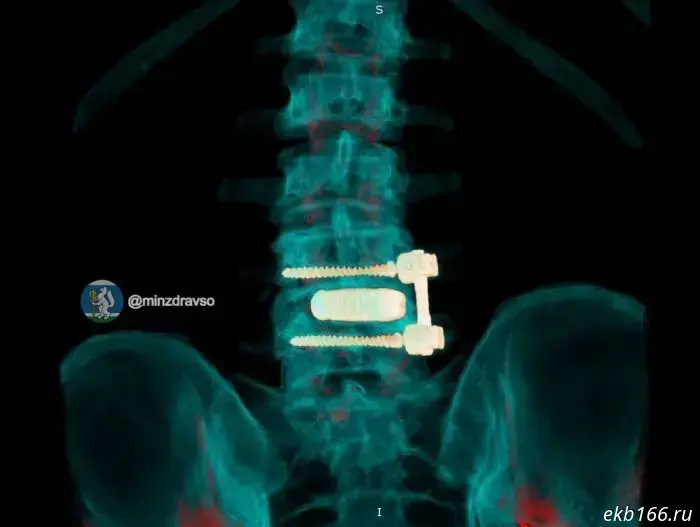

The man's problems began after a long-ago operation on the lumbar spine. His body began to reject the previously implanted metal construct, a peri-implant infection developed, and the patient's condition deteriorated rapidly. First the neurosurgeons removed the infected construct and debrided the focus of inflammation. The patient then underwent a course of intensive antibacterial therapy and preoperative preparation. Subsequently, a titanium 3D implant manufactured according to his individual anatomical parameters was implanted, and spinal fixation was performed using Russian cancellous screws.